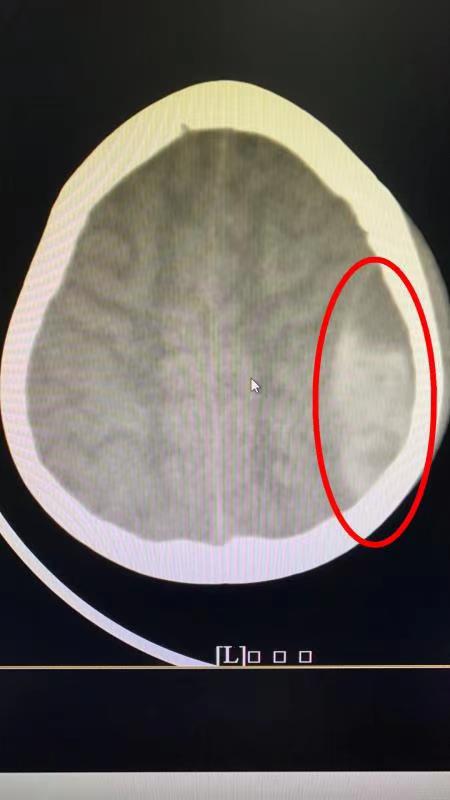

红圈内所示便是女童颅内左颞顶部硬膜外的大块血肿。

据了解,2月1日晚上,南方医科大学第三附属医院(简称南医三院)急诊接诊了一名6岁女孩童童,急诊科吴寿勉医生仔细询问病情得知孩子于4小时前从两米高的滑滑梯摔落,且头部着地,遂及时安排了头颅CT,检查结果提示患儿颅脑损伤,左侧颞叶、颞顶部硬膜外血肿。创伤救治中心负责颅脑外伤的手术团队,包括刘承勇主任、魏大年教授和宋振华主治医师立即查看了患儿情况,并与手术室沟通,安排患儿手术治疗,由于患儿病情危急,等待核酸结果有可能延误手术时机,只能采用标准三级防护开展急诊手术。